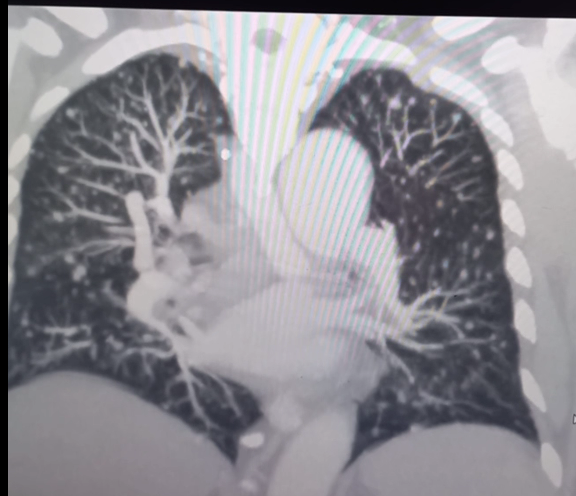

draurtecho Ago 19, 2024 Càncer de pulmòn El cáncer de pulmón en sus primeras etapas es en gran medida asintomático esto significa que los pacientes no se alertan ante cambios físicos obvios. Una vez que aparecen los síntomas, los pacientes suelen ignorarlos, lo que retrasa aún más el diagnóstico y el tratamiento. El cáncer de pulmón puede tardar hasta 8 años para tener un tamaño de 3 cm y con este tamaño, probablemente ya existan metástasis. Cuando existe un factor de riesgo como el tabaquismo, y síntomas que no son comunes, cómo pérdida de peso sin razón, toser la sangre etc. se debe realizar una radiografía de tórax y acudir al médico. La siguiente imagen, es un tipo de cáncer pulmonar en estado avanzado. No Comments InNeumología

draurtecho Ago 19, 2024 Càncer de pulmon El cáncer de pulmón en sus primeras etapas es en gran medida asintomático esto significa que los pacientes no se alertan ante cambios físicos obvios. Una vez que aparecen los síntomas, los pacientes suelen ignorarlos, lo que retrasa aún más el diagnóstico y el tratamiento. El cáncer de pulmón puede tardar hasta 8 años para tener un tamaño de 3 cm y con este tamaño, probablemente ya existan metástasis. Cuando existe un factor de riesgo como el tabaquismo, y síntomas que no son comunes, cómo pérdida de peso sin razón, toser la sangre etc. se debe realizar una radiografía de tórax y acudir al médico. La siguiente imagen, es un tipo de cáncer pulmonar en estado avanzado. No Comments InNeumología